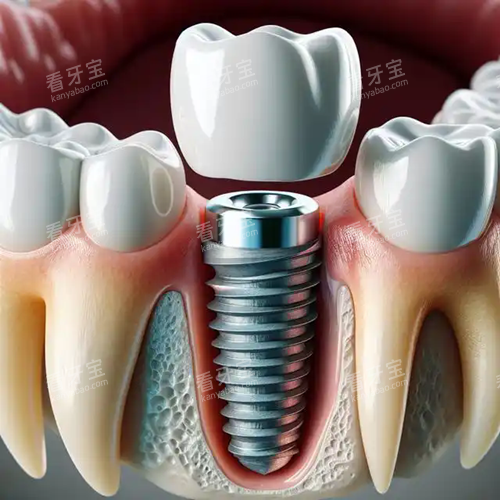

ЦЦЦІСАЧчОҒПЦөъСАүЖРЮёөµДёЯ¶ЛәәКхӘ¬ТФЖдОИ№МДНУГҰұҢУҢьЧФИ»САµДМШРФЙоКЬ»әХЯПІ°®ҰӘ